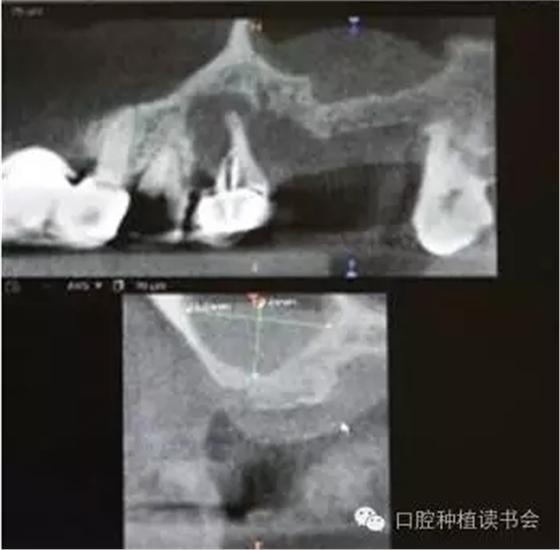

上頜后牙區(qū)牙槽脊吸收的特點(diǎn),主要是垂直高度的吸收。雖然牙槽脊垂直、水平吸收的程度幾乎相當(dāng),但是由于上頜后牙牙槽脊寬度較大,后牙區(qū)經(jīng)常出現(xiàn)圓鈍的、較寬的牙槽骨狀態(tài),臨床表現(xiàn)為剩余牙槽骨高度(Residual Bone Height,RBH)不足。在個(gè)別情況下,由于嚴(yán)重牙周病、根尖病等因素的影響,也會(huì)使牙槽脊水平寬度不足,表現(xiàn)為刃狀牙槽脊。上頜后牙一般為多根牙,當(dāng)牙周病和根尖病到一定程度后,磨牙才開(kāi)始松動(dòng)導(dǎo)致不能保留,又因上頜牙槽骨骨密度較低,在有些病例,牙槽脊重度吸收,RBH甚至不足1mm(圖1)。

▲(圖1)